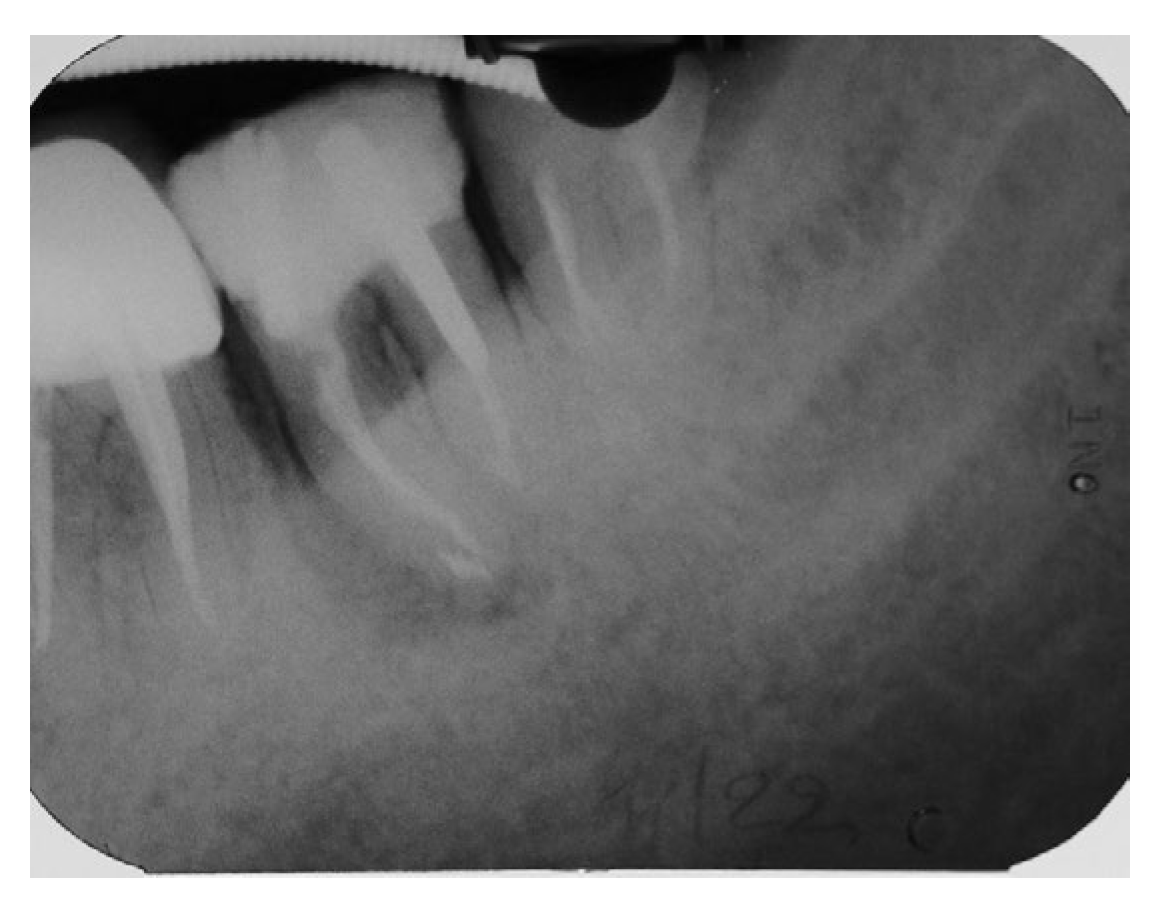

A periapical radiograph in the molar region of #46-47 teeth revealed that there was a radiolucent area in the middle third of the mesial root of tooth #47. This lesion was located mesially and it seems to be rather well defined in this area but coronally the bone loss had a J-shape appearance. In addition, subgingival carries in the distal roots of #47 and #46 were also detected (Figure 2). Both teeth had been restored with cast posts and splinted fused to metal ceramic crowns. Crestal bone between the two teeth appeared to be moderately resorbed.

Figure 2. Periapical X-Ray of #46, #47.